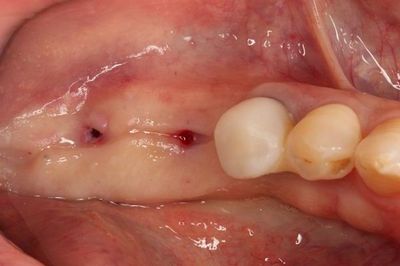

コラーゲンメンブレンの設置を終えました。

軟組織が移植材中に侵入することを防ぎ、骨増生(GBR)の成果を高めるために用います。

縫合を終えました。